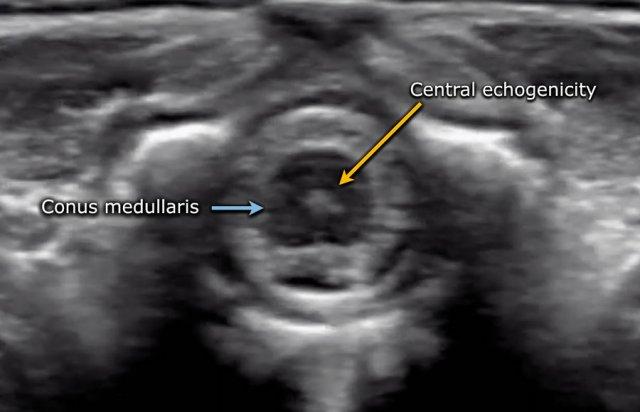

Tủy sống được hiển thị là một cấu trúc giảm âm rõ rệt với vùng tăng âm ở trung tâm.

Vùng tăng âm trung tâm này được cho là đại diện cho ranh giới giữa mép trước và rãnh giữa trước, chứ không phải ống trung tâm.

Hình ảnh cắt ngang tủy sống với vùng tăng âm trung tâm.

Đầu dưới của tủy phình to, đó là phình tủy thắt lưng.

Tủy thon dần thành một hình nón nhọn (mũi tên xanh).